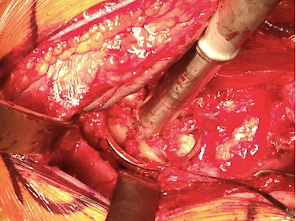

The glenoid was reamed to a diameter of curvature 4-6 mm greater than that of the selected humeral component, preserving as much subchondral bone as possible.